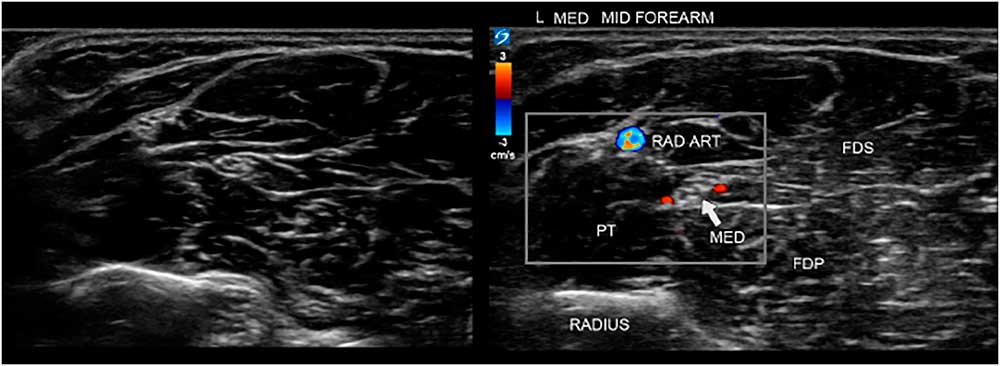

It is advisable to scan the whole nerve along its length, annotate the images, make measurements of nerve size and, if needed, mark the anatomical position. One should annotate each image with, at a minimum, the side measured (e.g., “L” for left), the nerve’s name (e.g., “med” for median) and, for longitudinal images, which side of the image was proximal (e.g., “prox”). If it is unclear from the image at which anatomical site it was taken, annotate that information in the image too (e.g., “distal carpal tunnel;” see Figure 7).

Figure 7 Two images of the ventral forearm. The left image is unannotated, making it harder to instantly recognize the site and anatomical features. On the right is the annotated image indicating the bone, muscles and median nerve for clarity, and also showing power Doppler signals of the radial artery (RAD ART) and small arteries accompanying the median nerve. FDP=flexor digitorum profundus; FDS=flexor digitorum superficialis; PT=pronator teres.